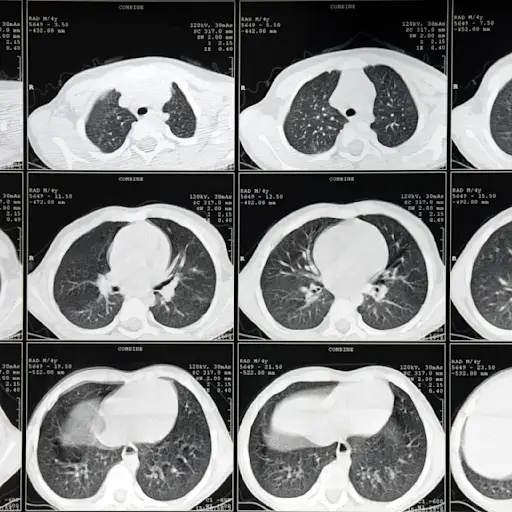

误解6:肺癌没有标准的筛查方法。

“许多初级保健医生不完全了解肺癌筛查的好处,所以他们不告诉病人——这是不好的,考虑到70%的筛查发现的肺癌处于早期阶段,因此是可以治愈的,”桑兹博士说。目前,只有2%符合每年低剂量CT扫描肺癌筛查标准的人接受了筛查。55岁至77岁才有资格;健康的相对健康的;每天(至少)抽20支烟,30年;或每天抽两包烟,15年;现在你吸烟;或者是在过去15年内戒掉的。